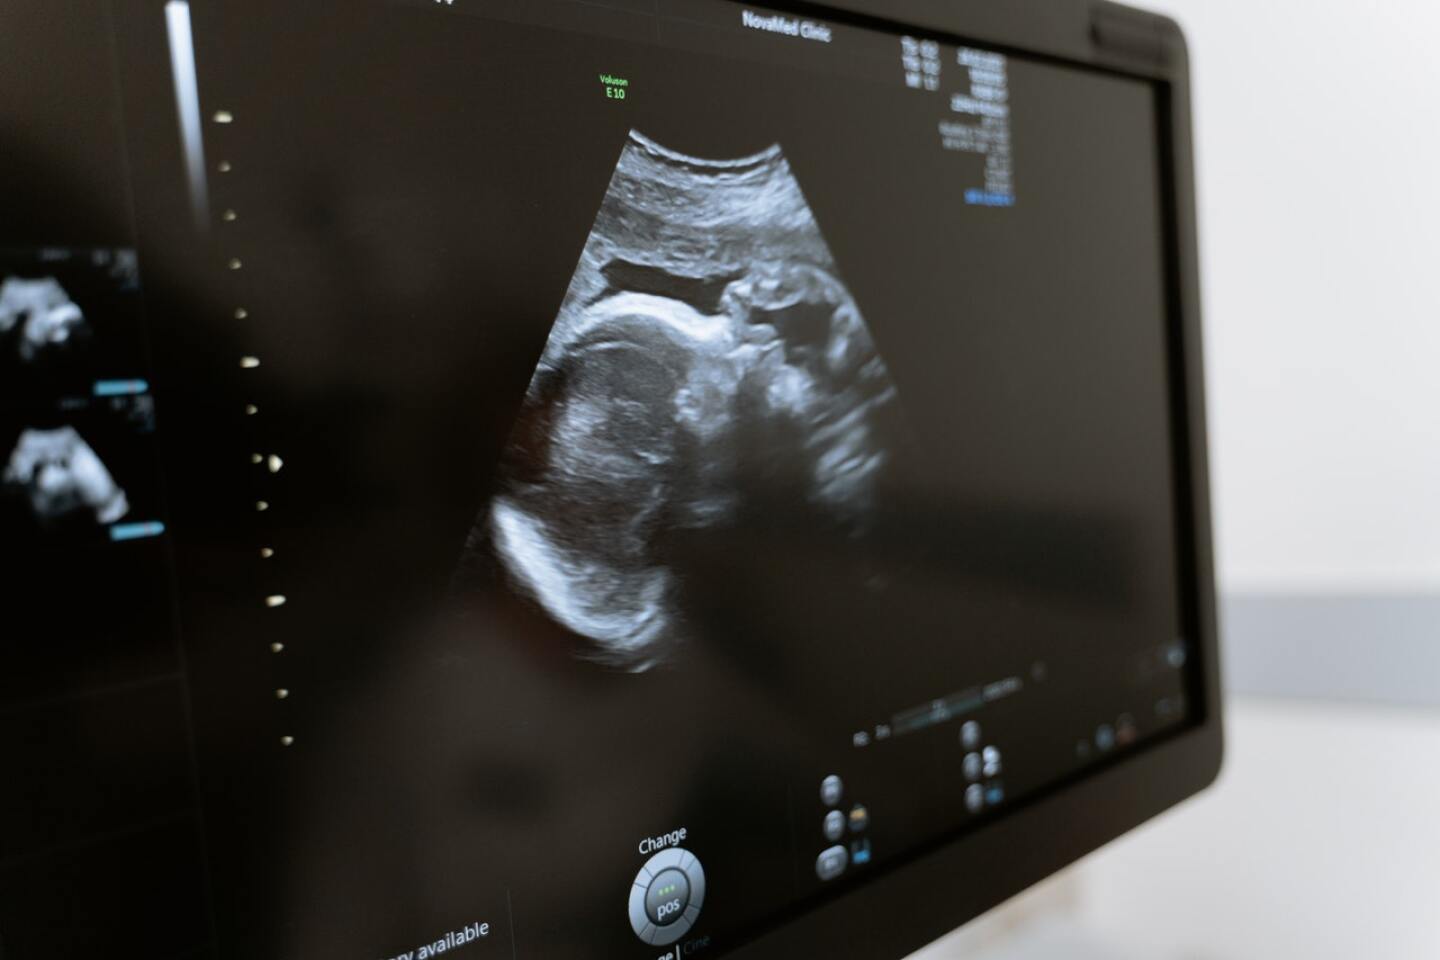

ultrasonido-embarazo

Foto: MART PRODUCTION en Pexels

Ver los movimientos y los gestos de un bebé no nato de una madre que fuma, uno o más cigarrillos al día, fue posible gracias a un estudio piloto que registró y observó –a través de imágenes en cuarta dimensión 4D– los gestos fetales de fetos de mamás fumadoras.

El estudio, elaborado por un grupo de investigadores británicos y publicado en Acta Pediátrica, consistió en observar y comparar, a través de ecografías de alta definición, los movimientos de fetos de mamás fumadoras y no fumadoras.

Un ultrasonido en cuarta dimensión es una técnica de diagnóstico prenatal que reconstruye de manera tridimensional las estructuras fetales en movimiento, como la cara, las manos o los pies.